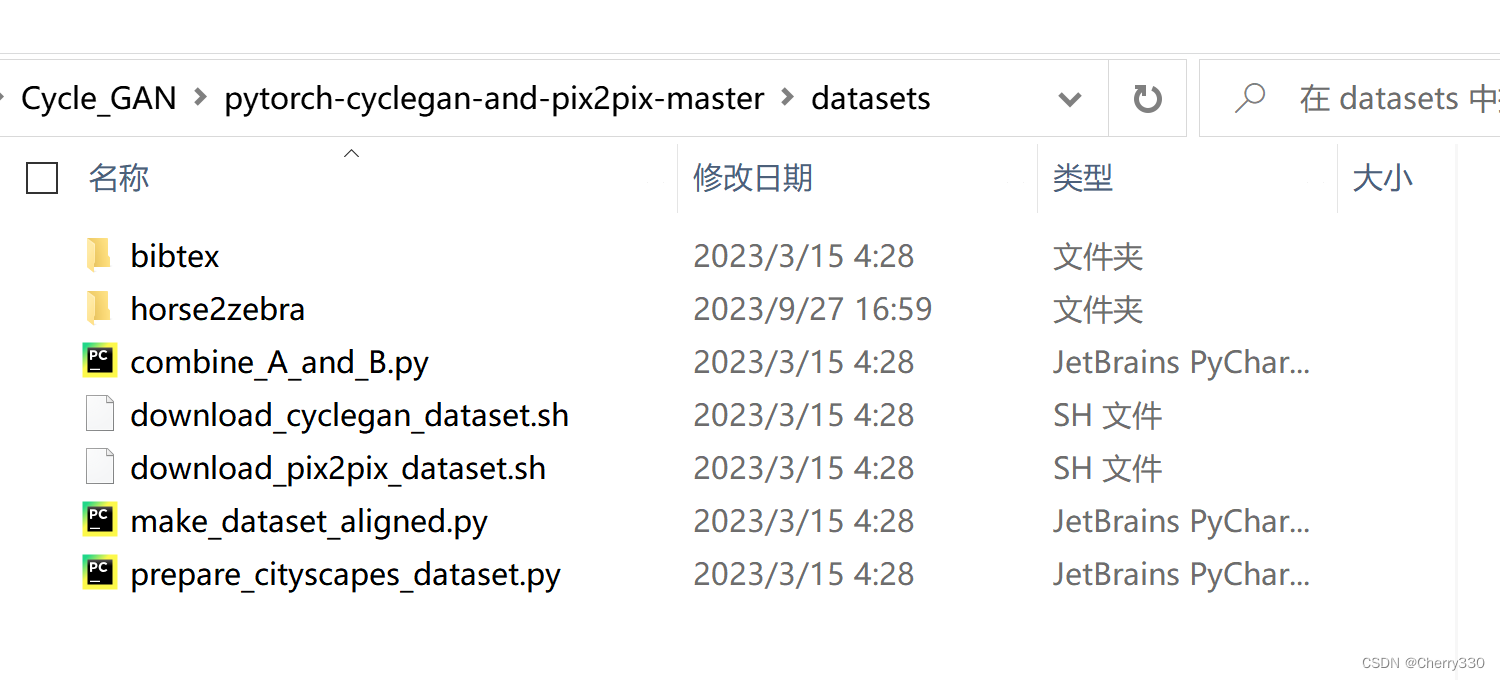

horse2zebra文件夹构成如下(图4)。大家将对应的图片放入文件夹中。数据集就完成啦~

需要注意的是,trainA和trainB是训练的数据集,testA和testB是测试的数据集,大家记得按照自己需求进行分配哦~ trainA和testA是需要转换的图片,就是我做的这个的T2图片,trainB和testB是风格图片,就是我的任务中的T1图片。如图5。

图4 horse2zebra文件夹构成

图5 数据集构成